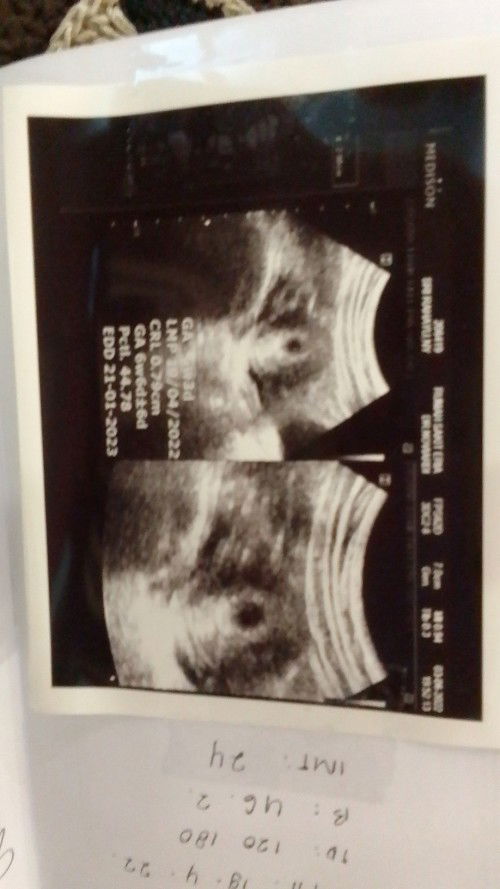

Bund mau nanya aku usg usia kandungan 6 minggu 3 hari Tapi masih terlihat kantung nya saja aman kah?

wajar bun, nnti di 7-9week baru ada janin bun